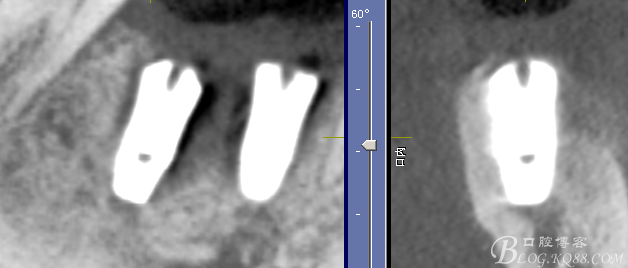

CT可見根管內(nèi)有白色顯影物和根周較大暗影

從根管影像看治療還是不錯(cuò)的,

懷疑牙根微裂,

所以建議患者手術(shù)探查

三維檢查種植體位置,方向,平行度